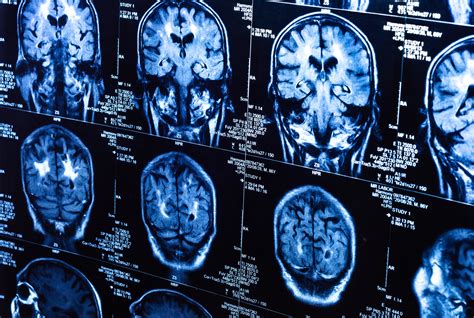

Computed Tomography (CT) scans use X-ray technology to create cross-sectional images of the brain. It is highly effective at identifying acute structural abnormalities. However, it is crucial to understand that a CT scan for concussion is primarily a safety screening tool, not a diagnostic test for the concussion itself.

Undergoing a CT scan for concussion is a relatively straightforward process. The patient lies on a motorized table that slides into a doughnut-shaped machine. The scanner rotates around the head, taking multiple X-ray images from different angles. The entire scan usually takes less than five minutes.

Because the procedure is fast, it is the preferred method for assessing patients who are agitated, confused, or physically unstable. Once the images are captured, they are reconstructed by a computer to allow a radiologist to examine the brain for signs of intracranial hemorrhage or hematoma (blood collection).